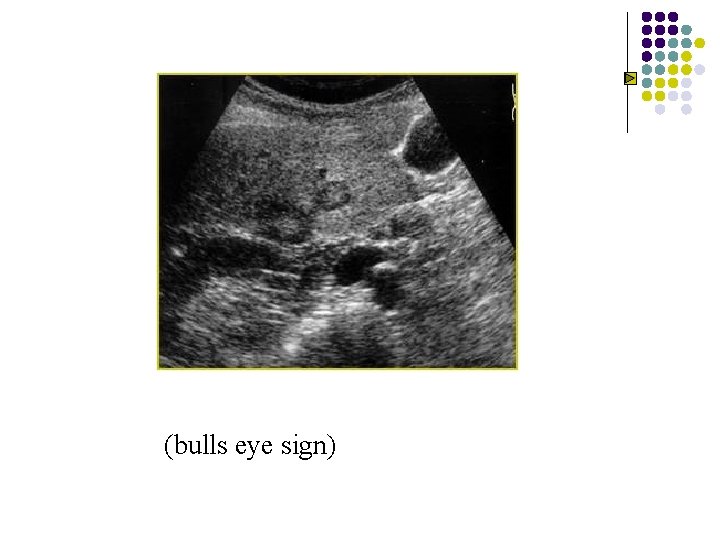

Metastases to liver l l l Organ of origin: colon(42%); stomach(23%); pancreas(21%); breast(14%); lung(13%) Number : multiple(98%); solitary(2%) “Bullseye”:An echogenic center with a surrounding echopenic area Echopenic : Less echogenic than the surrounding liver Echogenic More echogenic than the surrounding liver

“Bullseye”:An echogenic center with a surrounding echopenic area “牛眼征”

“Bullseye”:An echogenic center with a surrounding echopenic area

(bulls eye sign)